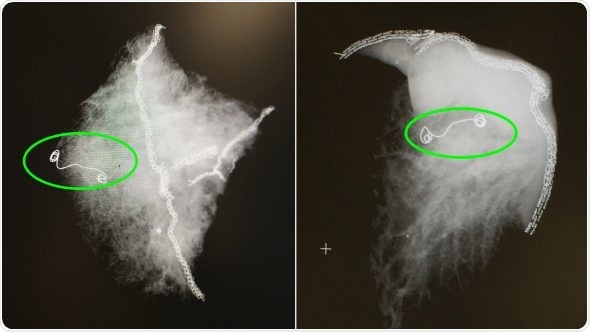

X-ray images of lung samples with the microcoil. (Courtesy: Cleveland Clinic)

Microcoil localization offered an alternative. The two-stage procedure typically proceeds in the following manner: after the patient goes to sleep in the operating room, a radiologist, using the hybrid operating room CT scanner and its advanced software capabilities, inserts a needle pre-loaded with a soft, fiber-coated platinum thread through the chest wall, then through the lung and finally, into the target nodule. This coil is carefully anchored to the nodule before the needle is removed.

Using video-assisted thoracoscopic technology (VATS), a thoracic surgeon locates the coil on the membrane around the lungs – the pleural surface – and carefully resects it along with the wedge of tissue containing the small nodule or lesion. The team can then instantly examine the tissue, make a diagnosis and, if necessary, perform further surgical treatment.